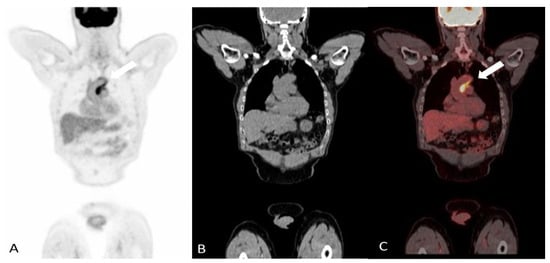

2.1.1. Giant Cell Arteritis